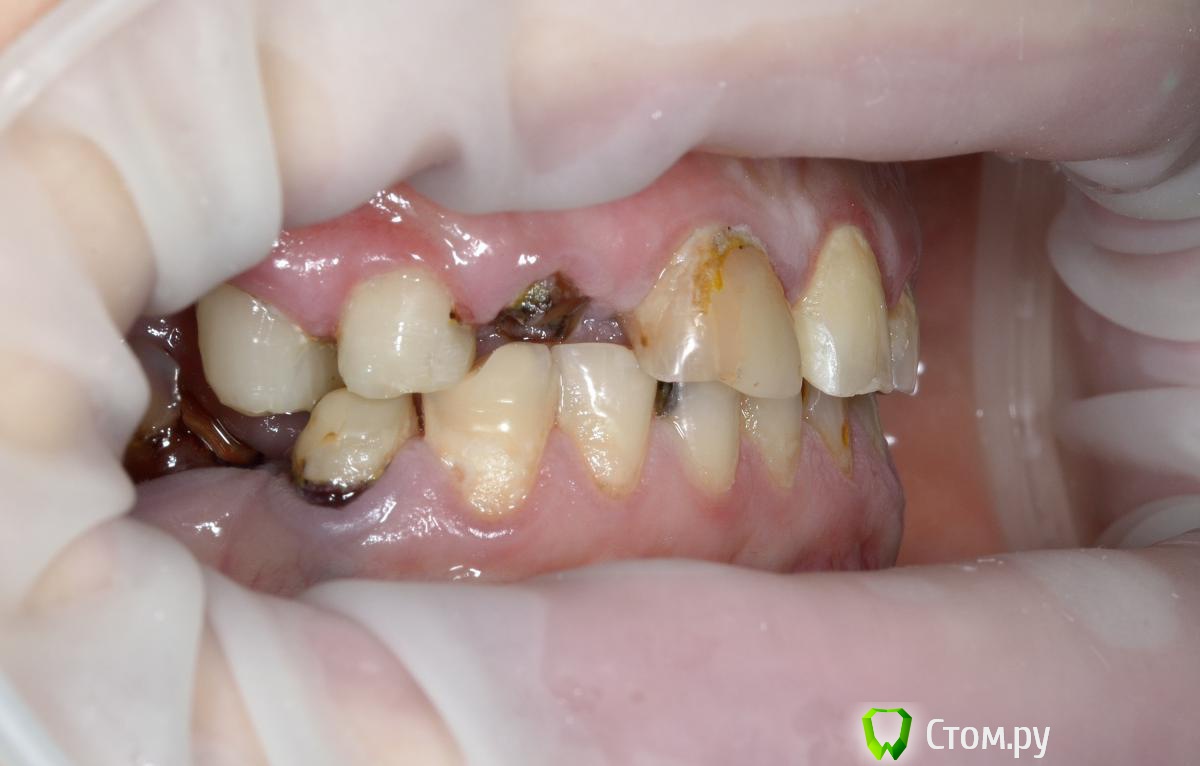

Vitremer Опубликовано 13 июля, 2014 Поделиться Опубликовано 13 июля, 2014 Здравствуйте! Пациентка 37 лет. Тотальное протезирование в/ч.Что делать:1.с уже ранее леченными и восстановлеными СВШ зубами 1.4 1.3 2.3 2.7 ? ( оставлять-менять на вкв...)2. корень 1.2 . ВКВ ? феррула почти нетПока такие вопросы. Ссылка на комментарий

Евгений Ходыкин Опубликовано 13 июля, 2014 Поделиться Опубликовано 13 июля, 2014 Имхо 1.7, 1.6, 1.2 аут, судьба остальных после рентгена... Ссылка на комментарий

Alex74 Опубликовано 13 июля, 2014 Поделиться Опубликовано 13 июля, 2014 (изменено) Давайте без сарказма. Пока она будет собирать на две челюсти-полетит все оставшееся. А импланты-совсем другой прайсНикакого сарказма. БОльшая часть зубов, судя по фото, очень сильно разрушена. Качественно их сделать будет стоить не дешевле имплантатов. Если перебирать их дорого, то тогда "более-менее" нормальные зубы - это резцы 11 21 22 и премоляр слева. Какие варианты бюджетные приходят в голову с 4 оставшимися во рту зубами? А ставить "на то что было, то и полюбила"...ну не знаю. Сколько оно простоит? Поэтому простое решение предложил - всё убрать и сделать ПСП. Изменено 13 июля, 2014 пользователем Alex74 Ссылка на комментарий